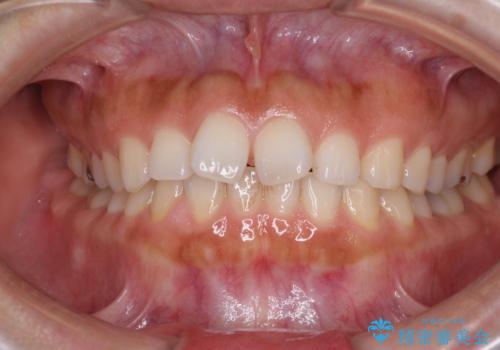

前歯のがたつき 深い噛み合わせを改善したい